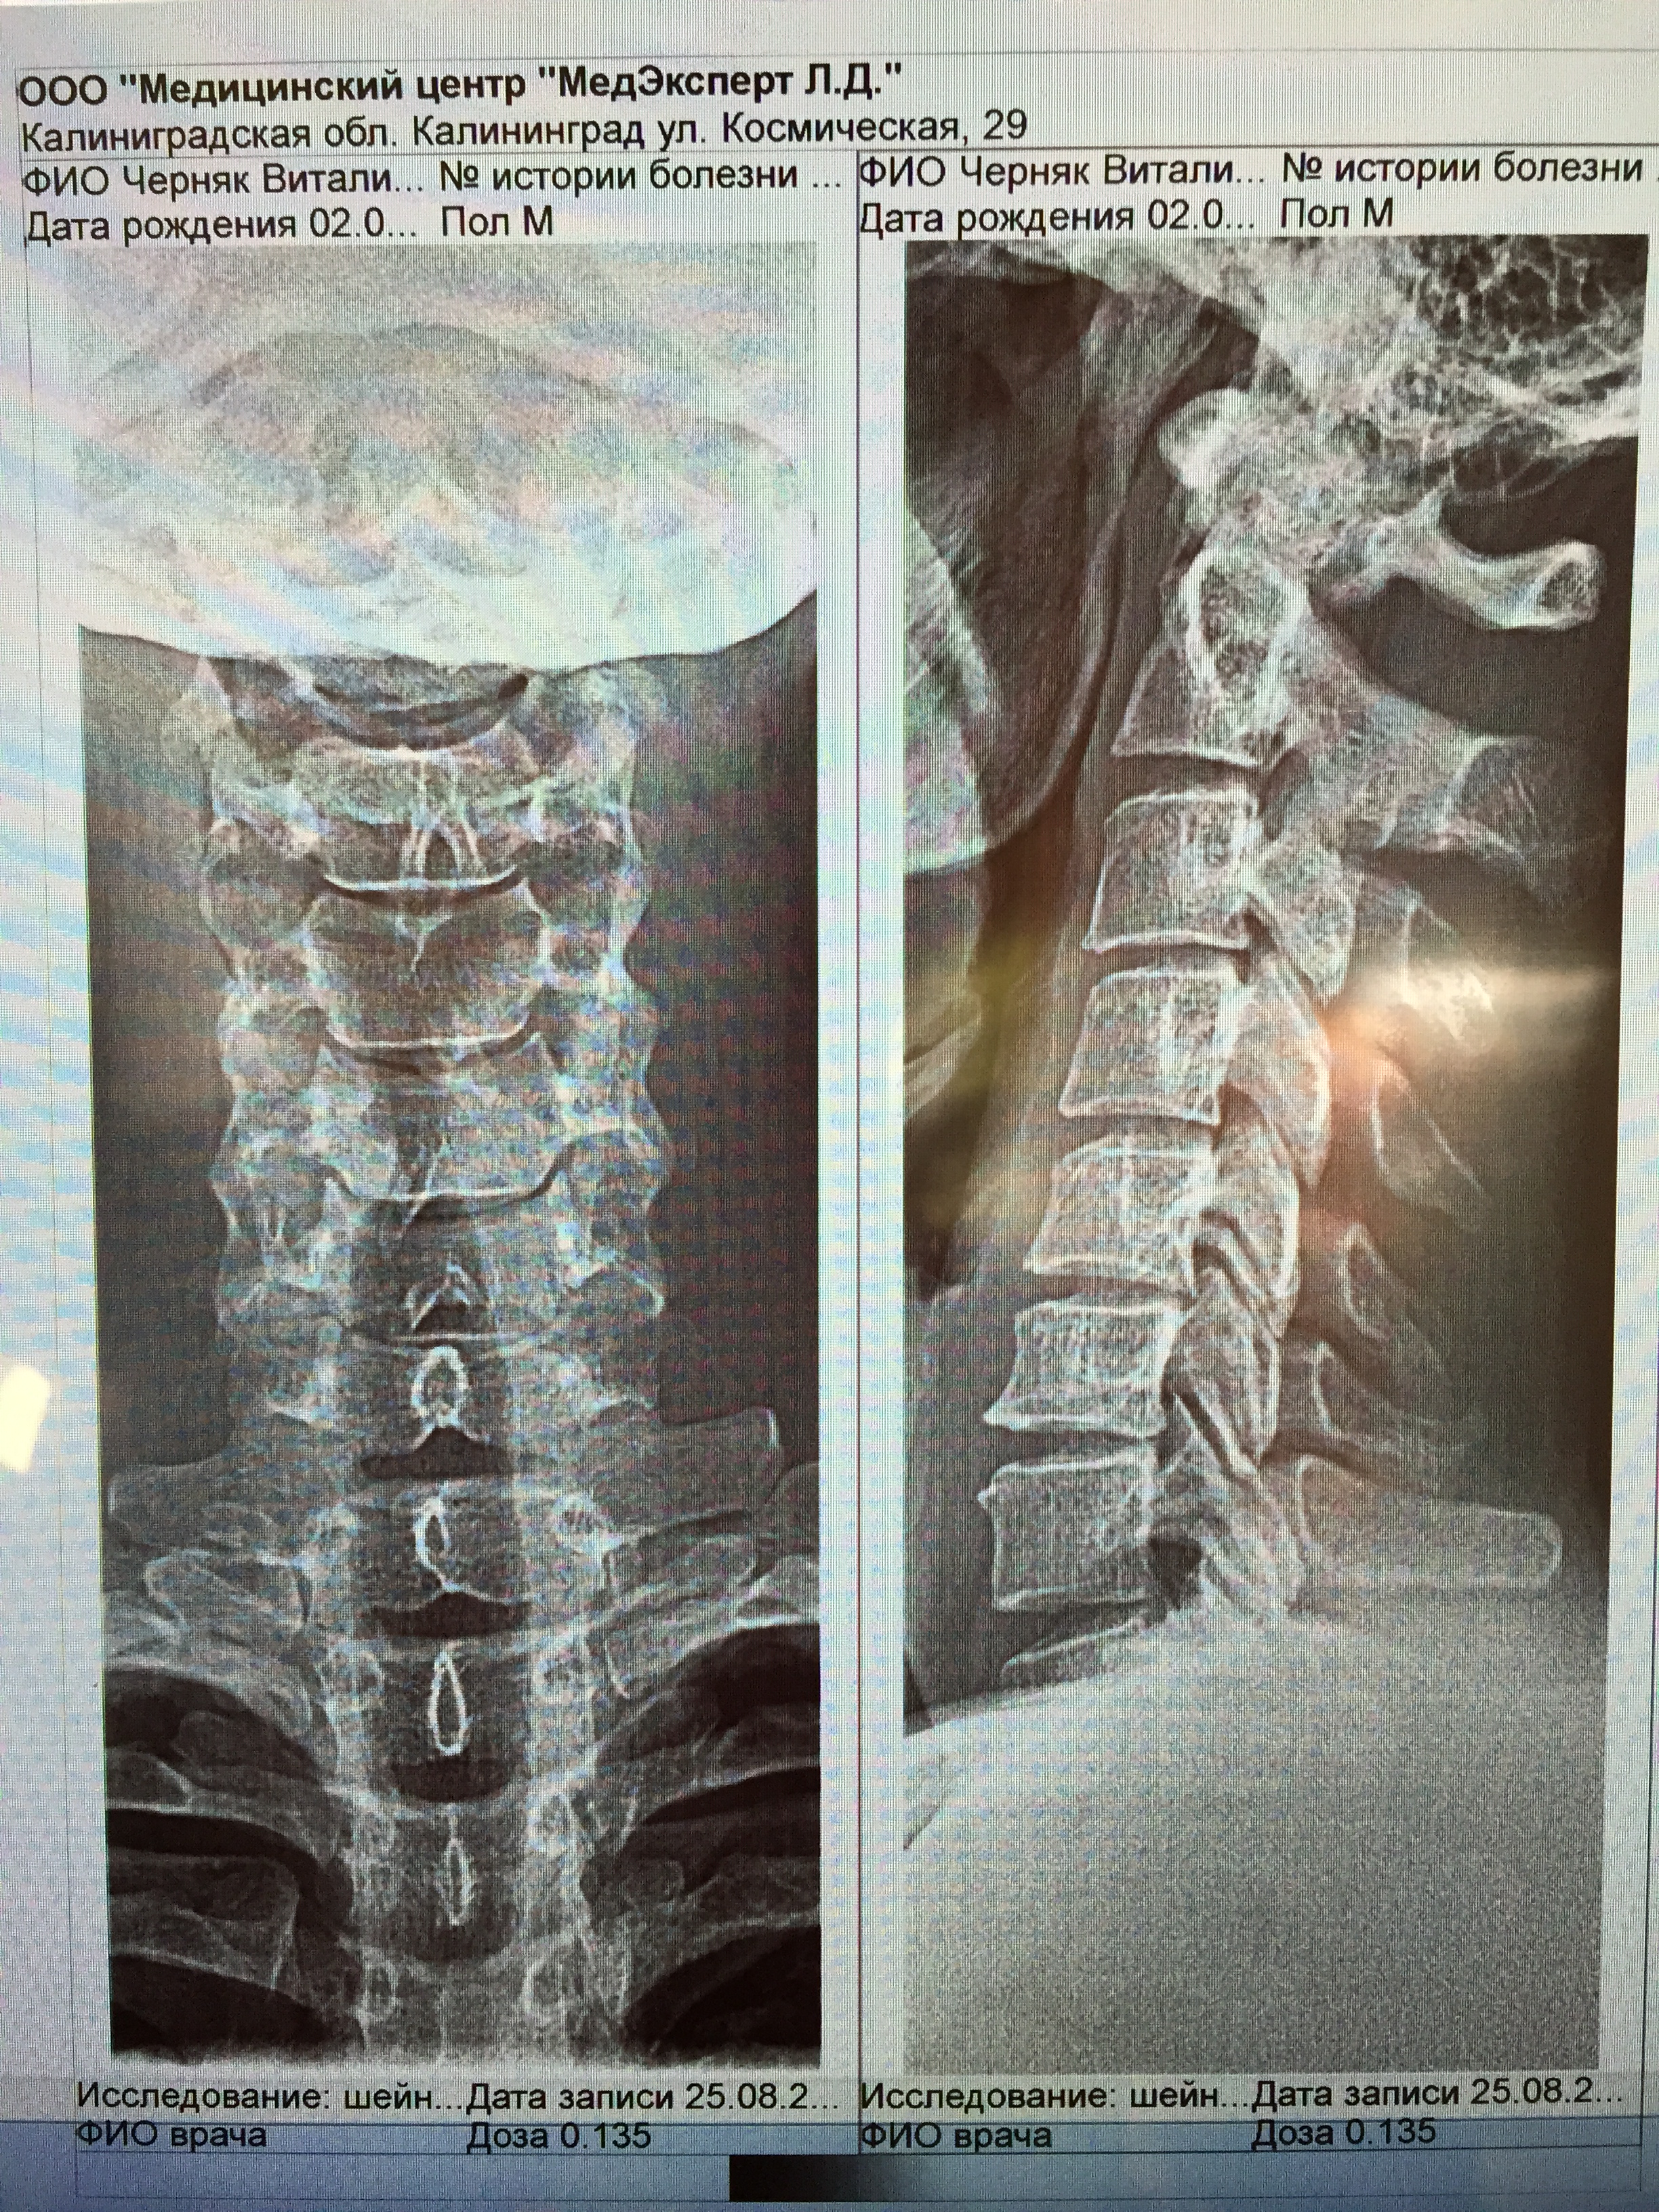

- постоянные непрекращающиеся боли в шее, затылке, переходящие в височную область и голову выше,

- чувство давления и распирания в подзатылочной области,

- чувство стянутости по всей шее, в т.ч. спереди,

- появилось ощущение "мурашек" или, точнее, как будто волос щекотит по шее.

- после физ. нагрузок чувство воспаления по всей шее.

Ощущаю постоянное напряжение подзатылочных мышц и хрусты чуть ниже. Нестабильность с2-с3? Хрусты разного характера справа и слева. Хрусты сильные, ощущения, будто позвонки "гуляют". Пару раз было ощущение смещения позвонка с сильным хрустом и прострелом "током". После - шея каменная. Посреди шеи сзади появилось уплотнение, как шарик, который при пальпации перемещается... Головная боль в височной области, стал ощущать пульсацию и давление в районе носовых пазух и скулах верхней челюсти.

Вы 84 г.р., для серьезных проблем с ШОП рановато. По снимкам - показаний к нейрохирургической коррекции нет. Обычно мы проводим периодические поддерживающие курсы консервативного лечения, которые позволяют снизить или убрать кранио-цервикалгию (боль в шее голове). От пациента требуется выполнение ежедневной лечебной физкультуры, это за Вас никто не сделает. Если надумаете пройти лечение у нас, можно обратиться по тел 900-39-76 по раб дням с 9-15.